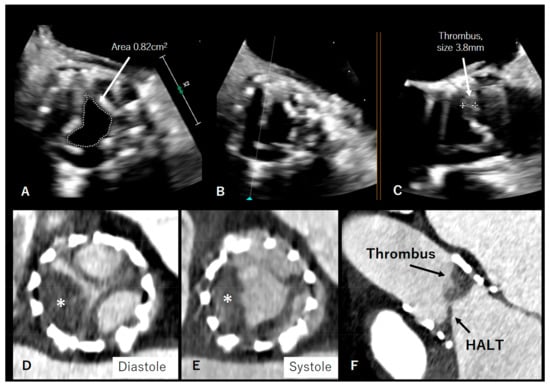

4. Valve Thrombosis/HALT/Pannus